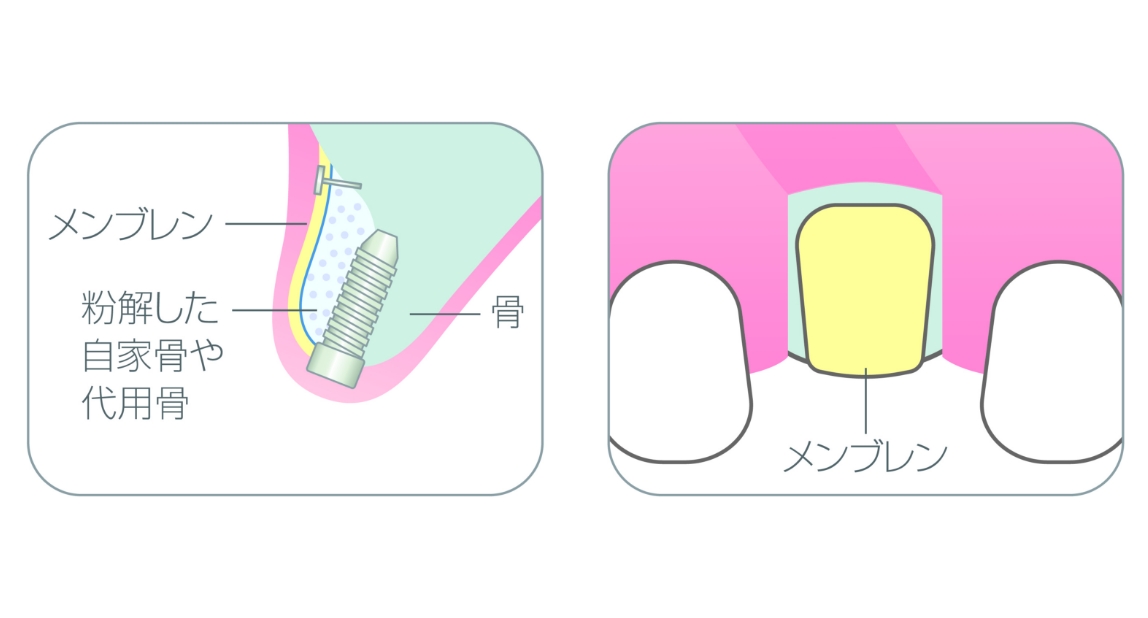

「ノーベルガイド」は、歯肉を切開せずにインプラントを埋入するノーベル独自のガイドシステムです。術前のデジタルシミュレーションとガイドテンプレートで正確な埋入と低侵襲な手術を実現し、患者様のご負担を軽減します。